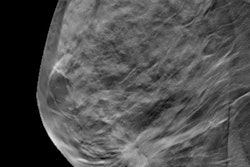

While AI is being applied to various imaging modalities, it appears to be a perfect match for DBT. Also known as 3D mammography, DBT offers a number of improvements over traditional 2D full-field digital mammography (FFDM) in terms of cancer detection, but it also presents unique challenges that lend themselves well to AI, such as higher radiation dose and longer interpretation times.

One of the most serious challenges with DBT has been radiation dose. Breast imagers have found 3D mammography to be tremendously useful for detecting cancer, but many do not want to part with the 2D views they've come to rely on from traditional mammography. Performing another exam to provide those views boosts radiation dose to patients -- a major concern in any screening environment.

Synthesized 2D mammography is a possible solution by enabling 2D-like images to be reconstructed from the slices acquired with a 3D exam, cutting dose by 50%. But how well does AI perform when examining synthesized 2D data?